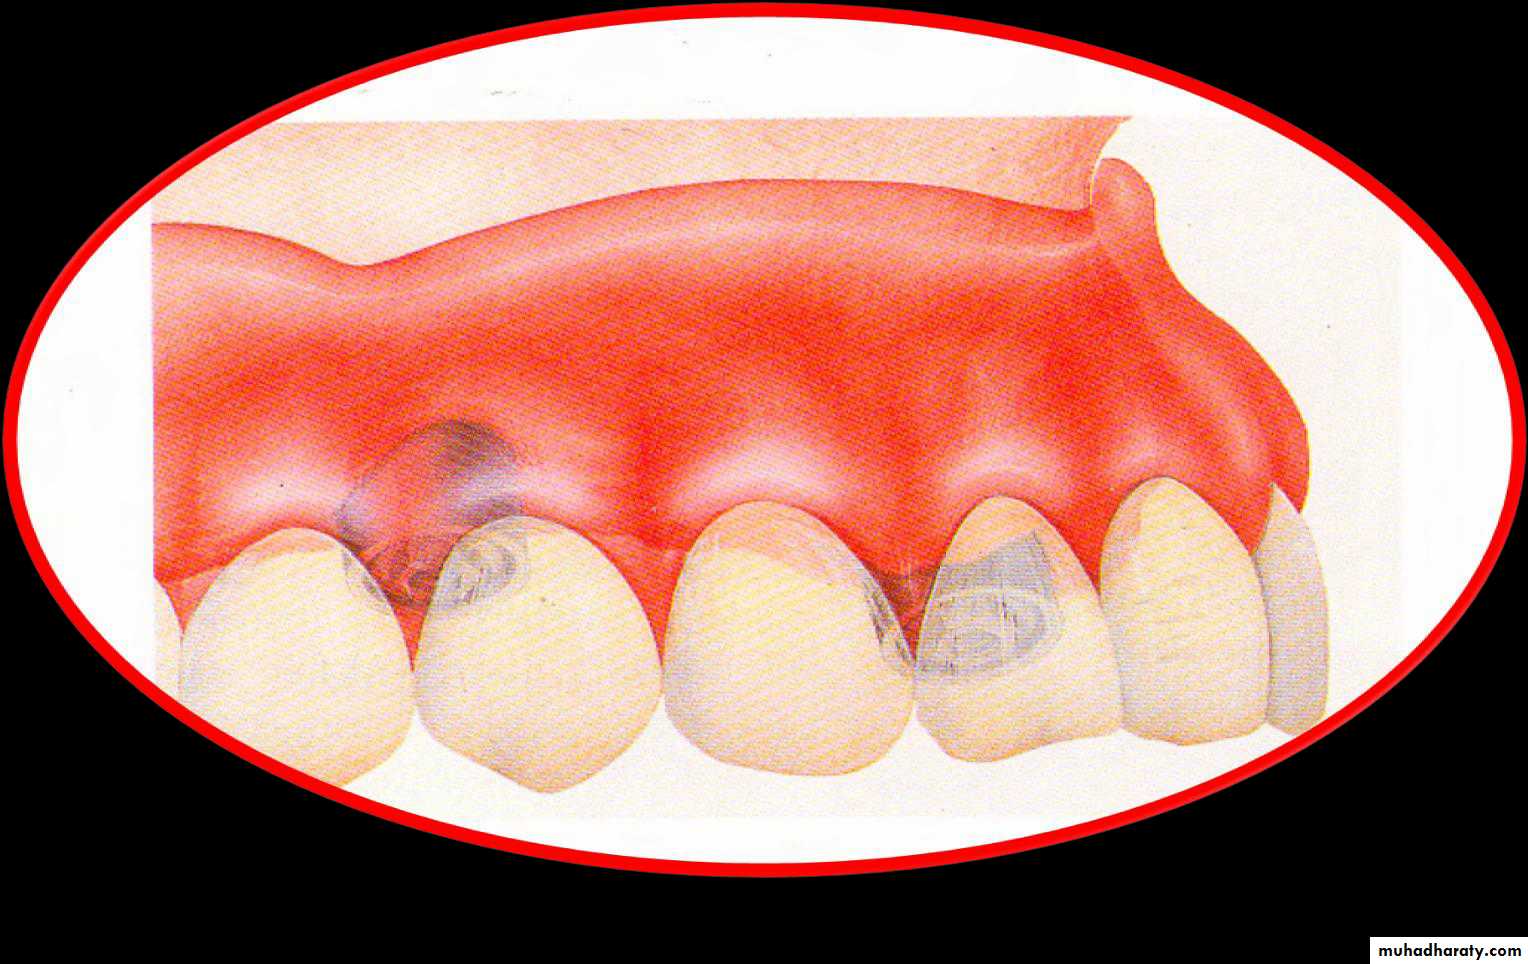

• 1) Preservation of the alveolar ridge.

• 2) Enhanced retention of the tooth in the jaw

• (reduced C/R ratio)• 3) Enhancement and maintenance of denture

• stability .• 4) Maintenance of the patient’s neuromuscular control and prevention of masticatory muscle atrophy .